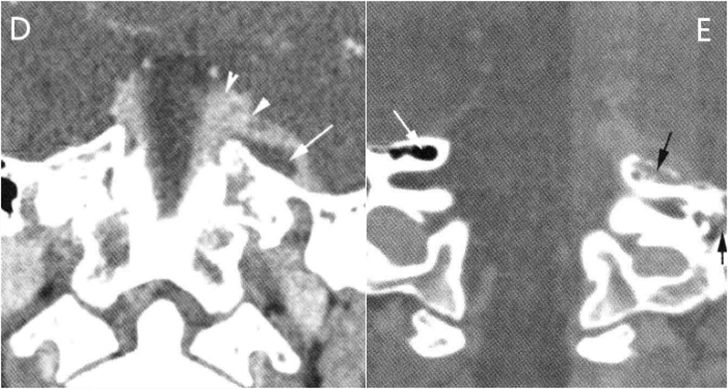

图D冠状面图像显示硬膜外脓肿(箭)和弥漫的硬脑膜蜂窝织炎。

图E图中正常侧所示的气房(白箭)是此病的扩散路径,中耳和乳突疾病可以通过此气房扩散到岩尖(黑箭)。